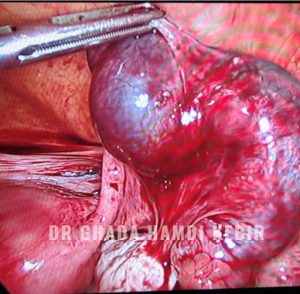

Le traitement d’un kyste organique repose sur la chirurgie par l’ablation chirurgicale du kyste (kystectomie ovarienne) ou de l’ovaire (ovariectomie). Cette opération est généralement réalisée par cœlioscopie.

La myomectomie consiste à retirer le ou les fibromes tout en conservant l’utérus. C’est donc une intervention chirurgicale conservatrice. L’ablation du fibrome peut être réalisée par :

• Cœlioscopie. Elle est effectuée comme pour l’hystérectomie mais elle se limite à l’extraction de(s) fibrome(s).